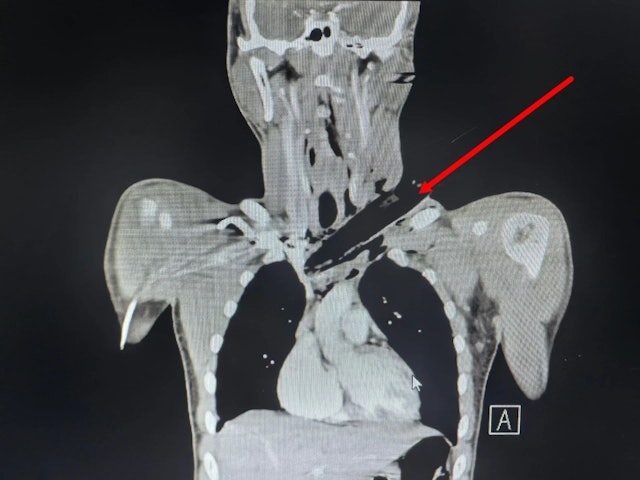

(陕西15日综合电)陜西西安青年小易早前在一个工地上突遇恐怖意外,一条直径约3公分的枯枝从高处铁落,自左侧颈部斜向右下贯入后直达胸腔,深入人体约12公分,被紧急送入空军军医大学唐都医院急诊科。

空军军医大学唐都医院披露,一根直径约3公分的枯枝从高处掉落,自小易的左侧颈部斜向右下贯入直达胸腔。影像学检查显示,枯枝前方紧邻左无名静脉,后方压迫主动脉弓分支,远端贴近上腔静脉,任何一处血管破裂都将瞬间致命。

手术开始后,医生发现枯枝自左侧颈部斜向内下方刺入前上纵隔,前方紧贴左无名静脉,后方毗邻被外科医生称为“三根毛”和主动脉弓分支(主动脉弓为主动脉上部的弓形部分,弓顶有3条大动脉,负责人体部头、上肢血供),远端更与上腔静脉仅融数毫米,然而这些血管竟然完好无损,“看着很吓人,其实哪都没伤到!”